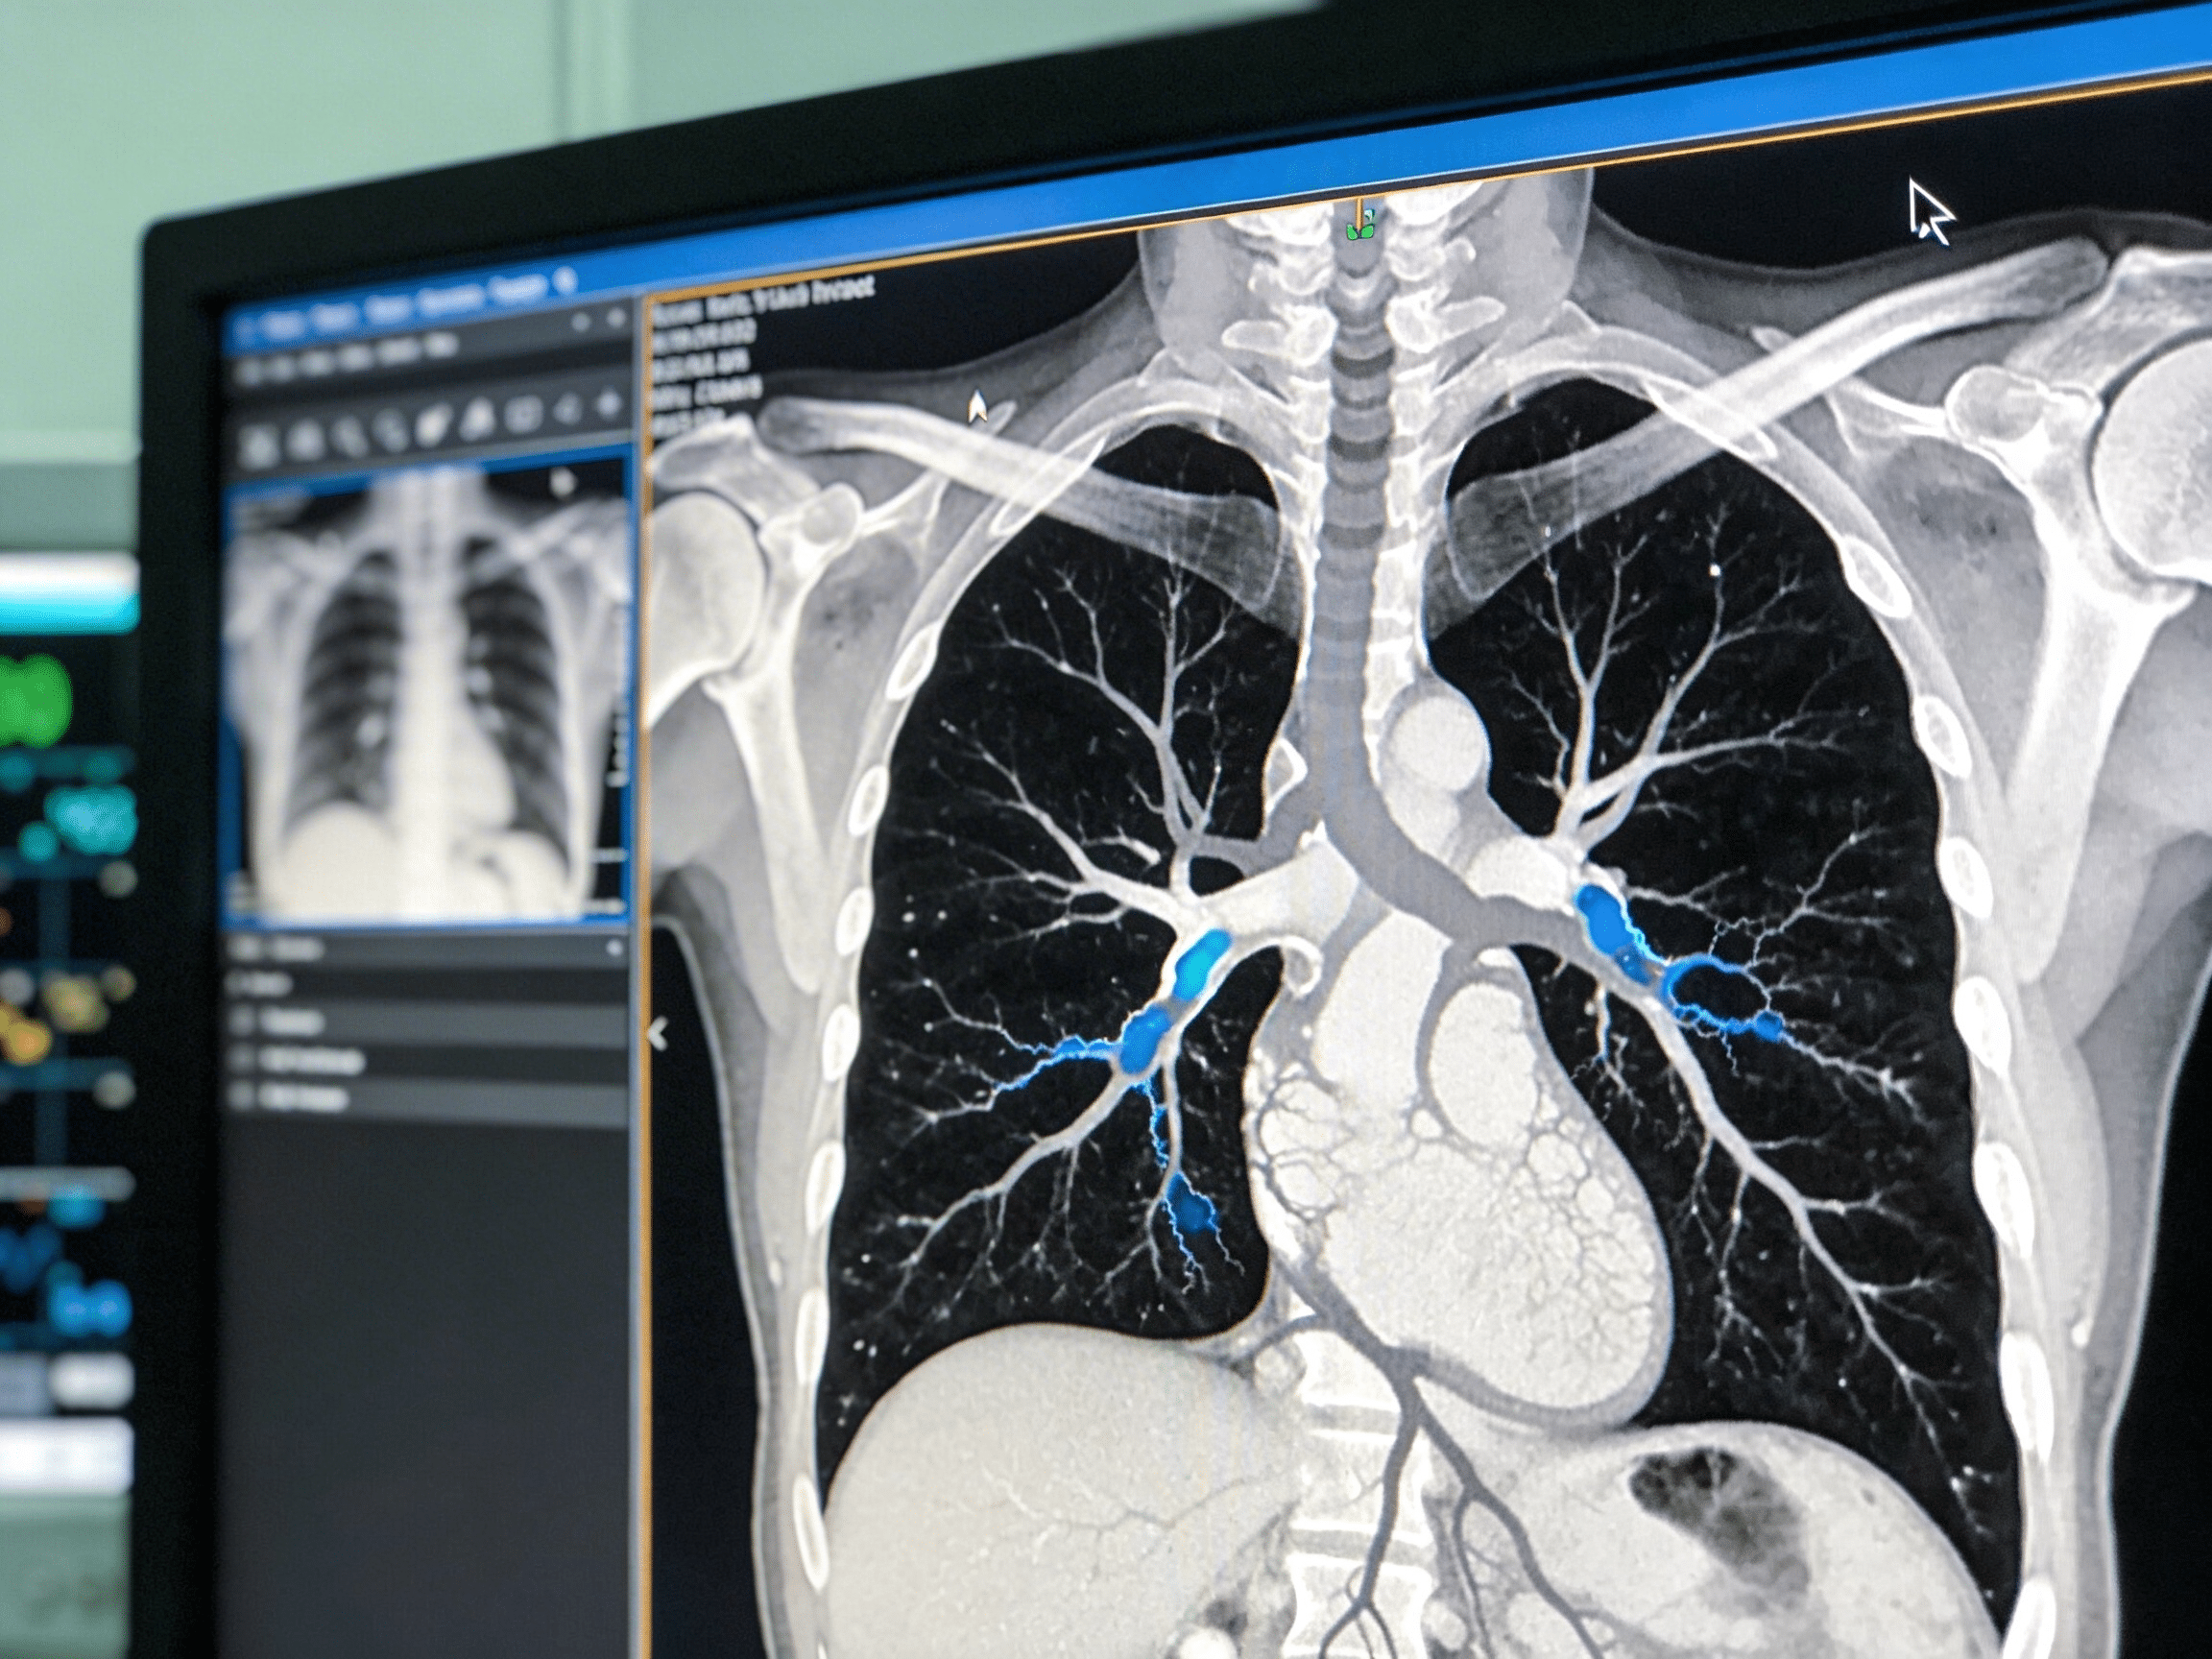

Emergency chest X-ray and CT angiogram equipment at Priority ER Odessa

State-of-the-art chest imaging equipment available 24/7 at Priority ER for immediate respiratory evaluation

Priority ER's diagnostic capabilities for chest X-ray & CT angiogram for pneumonia, pneumothorax, or PE exceed Joint Commission standards for emergency departments[14], featuring digital portable chest radiography enabling immediate bedside imaging for unstable patients without transport to radiology, multidetector CT with IV contrast pulmonary angiography protocol detecting filling defects in pulmonary arteries with 96% sensitivity, and immediate emergency physician interpretation identifying pneumonia infiltrates, pneumothorax, and pulmonary embolism within 15 minutes. Our emergency physicians trained in chest imaging interpretation apply Wells criteria (clinical probability scoring) and PERC rule (Pulmonary Embolism Rule-out Criteria) determining which patients require CT angiography versus alternative diagnoses, preventing unnecessary radiation while ensuring PE diagnosis when clinically indicated[15]. The integration of right heart strain assessment on CT (RV/LV ratio >1.0) identifies massive PE requiring thrombolytic consideration, while identification of pneumonia complications including empyema, lung abscess, or necrotizing pneumonia guides surgical consultation.

Advanced assessment through our comprehensive diagnostic capabilities provides ventilation-perfusion (V/Q) scanning coordination when CT contraindicated by renal insufficiency or contrast allergy, echocardiography assessing right ventricular dysfunction when massive PE suspected, and bronchoscopy consultation when pneumonia complicated by suspected foreign body aspiration or endobronchial obstruction. For pneumothorax evaluation, our emergency physicians measure pneumothorax size using British Thoracic Society guidelines (distance from lung apex to cupola) determining whether observation, aspiration, or chest tube placement indicated, with immediate intervention for tension pneumothorax presenting with tracheal deviation, hypotension, and absent breath sounds requiring needle decompression before radiographic confirmation. This comprehensive approach explains why the American College of Radiology appropriateness criteria mandate chest X-ray as first-line imaging for pneumonia and pneumothorax, with CT angiography reserved for PE diagnosis providing definitive visualization of thrombus location and burden guiding anticoagulation versus thrombolytic therapy.